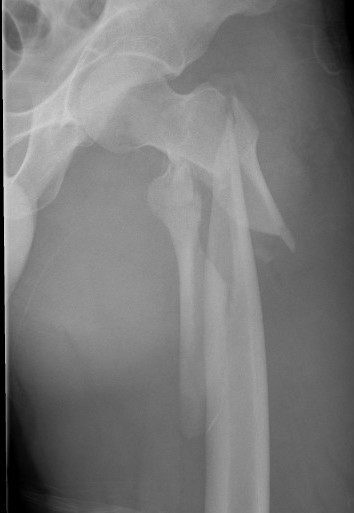

Definition

Fracture below lesser trochanter

Proximal 5 cm femoral shaft

AO classification

32-A3: Short transverse

32-B3: Wedge, fragmented

32-C1: Spiral, complex